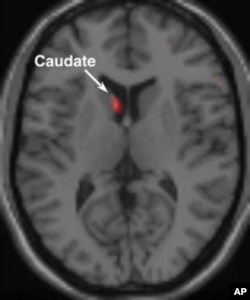

The caudate nucleus portion of the brain, which is associated with passion, becomes aroused when someone is shown a picture of a person with whom he or she is in love.

Without exception, the picture stimulated heightened electrical activity in two key areas of the brain: the caudate nucleus and ventral tegmental area.

Brown – a professor at Albert Einstein College of Medicine - says these two regions comprise the brain’s reward system. A primitive part of the organ also found in other mammals, it is more closely associated with the desire for food and water than with the sex drive.